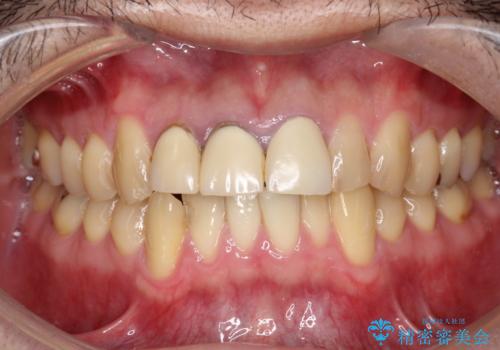

20代男性 セラミックインレーによる歯の形態修復

他院にて矯正中、歯の生理的な形態を考えないディスキング(歯のサイズダウン)をされ、いびつな形態となっていた歯を、セラミックインレーにて形態回復しました。

詰め物の種類:e.max プレスインレー